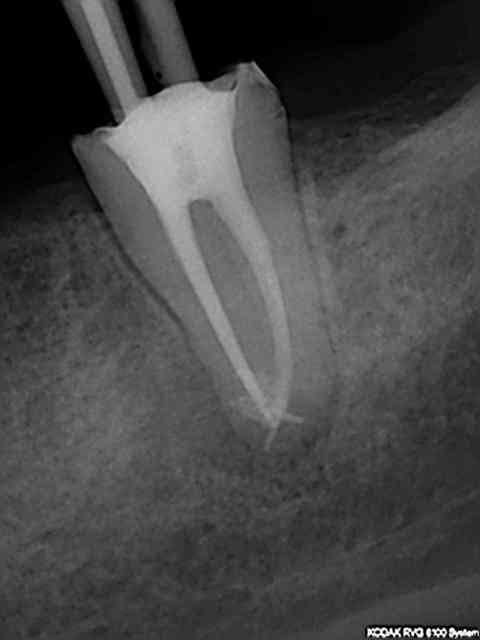

J'utilise le système heroshaper+digue+hypo+condensation

Mac Spadden(thermomécanique)

J'ai posté des radios biopulpectomies et retraitements

canalaires précédemment.

L'obturation 3D est indispensable pour un traitement hermétique.Mon associé utilise le système protaper et

effectivement cela élargit plus.Sur ces 7 dernières années

j'obtiens de bons résultats;mon avis le système heroshaper

casse moins mais n'hésite pas à jeter un heroshaper

même si non déspiralé ;si il a travaillé un peu en force

ou si la morphologie canalaire est un peu compliquée ou courbe;on fait un peu un usage unique pour éviter tout

problème plus tard!(quelque soit le système)on récapitule

avec un instrument à mains;pour une bonne herméticité

le système Mac spadden est le plus efficace ,utlisé par des endos exclusifs,et le moins cher (un cone de gutta est suffisant)Ma séquence classique instrument à main N10

héroshaper N20 6%/4% N25 4% N30 4% MAC SPADDEN un cone de gutta/ciment sealite régular

J'ai reposté quelques radios de biopulpectomies

RTE dans un précédent post...